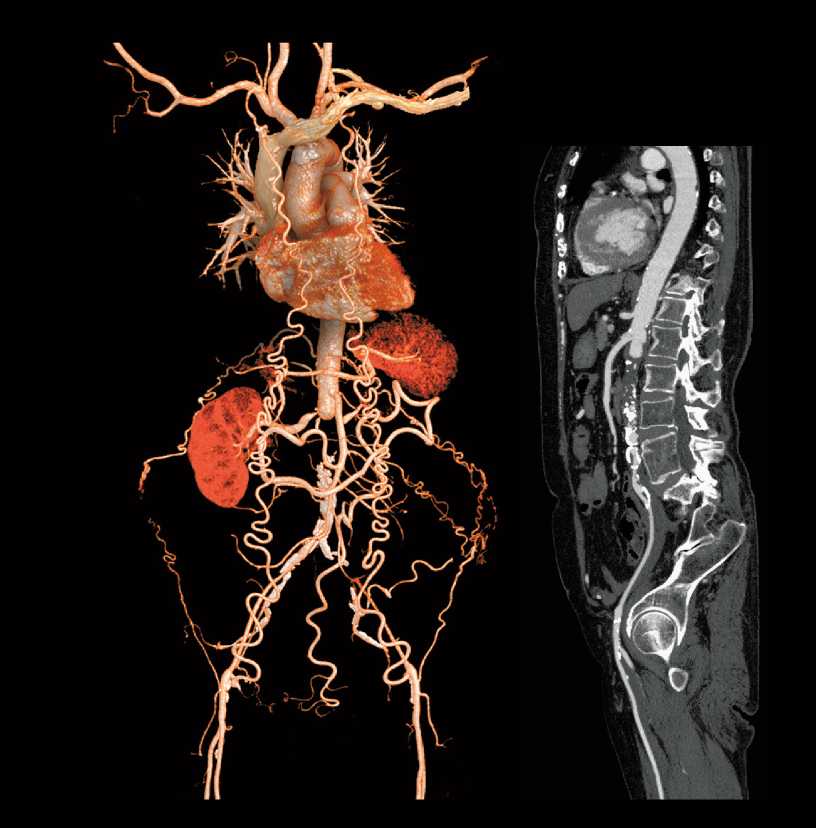

Abdominal aortic occlusion

Intraoperative oxygen desaturation (Left)

Left common iliac artery occlusion (Right)

- * Images other than the axial image were processed by the 3D image analysis system SYNAPSE 3D.